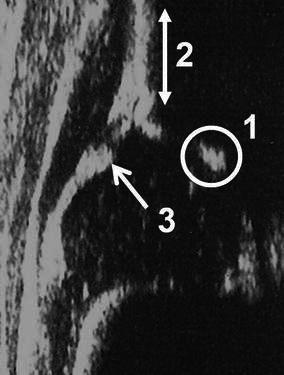

Fig. 3.

Standard plane for the Graf method [4]. 1 The lower limb of the ilium is clearly visible. This means that the sectional plane passes through the centre of the acetabulum. 2 A straight iliac wing silhouette exists. This means that the probe is parallel to the iliac bone. 3 The labrum is clearly visible